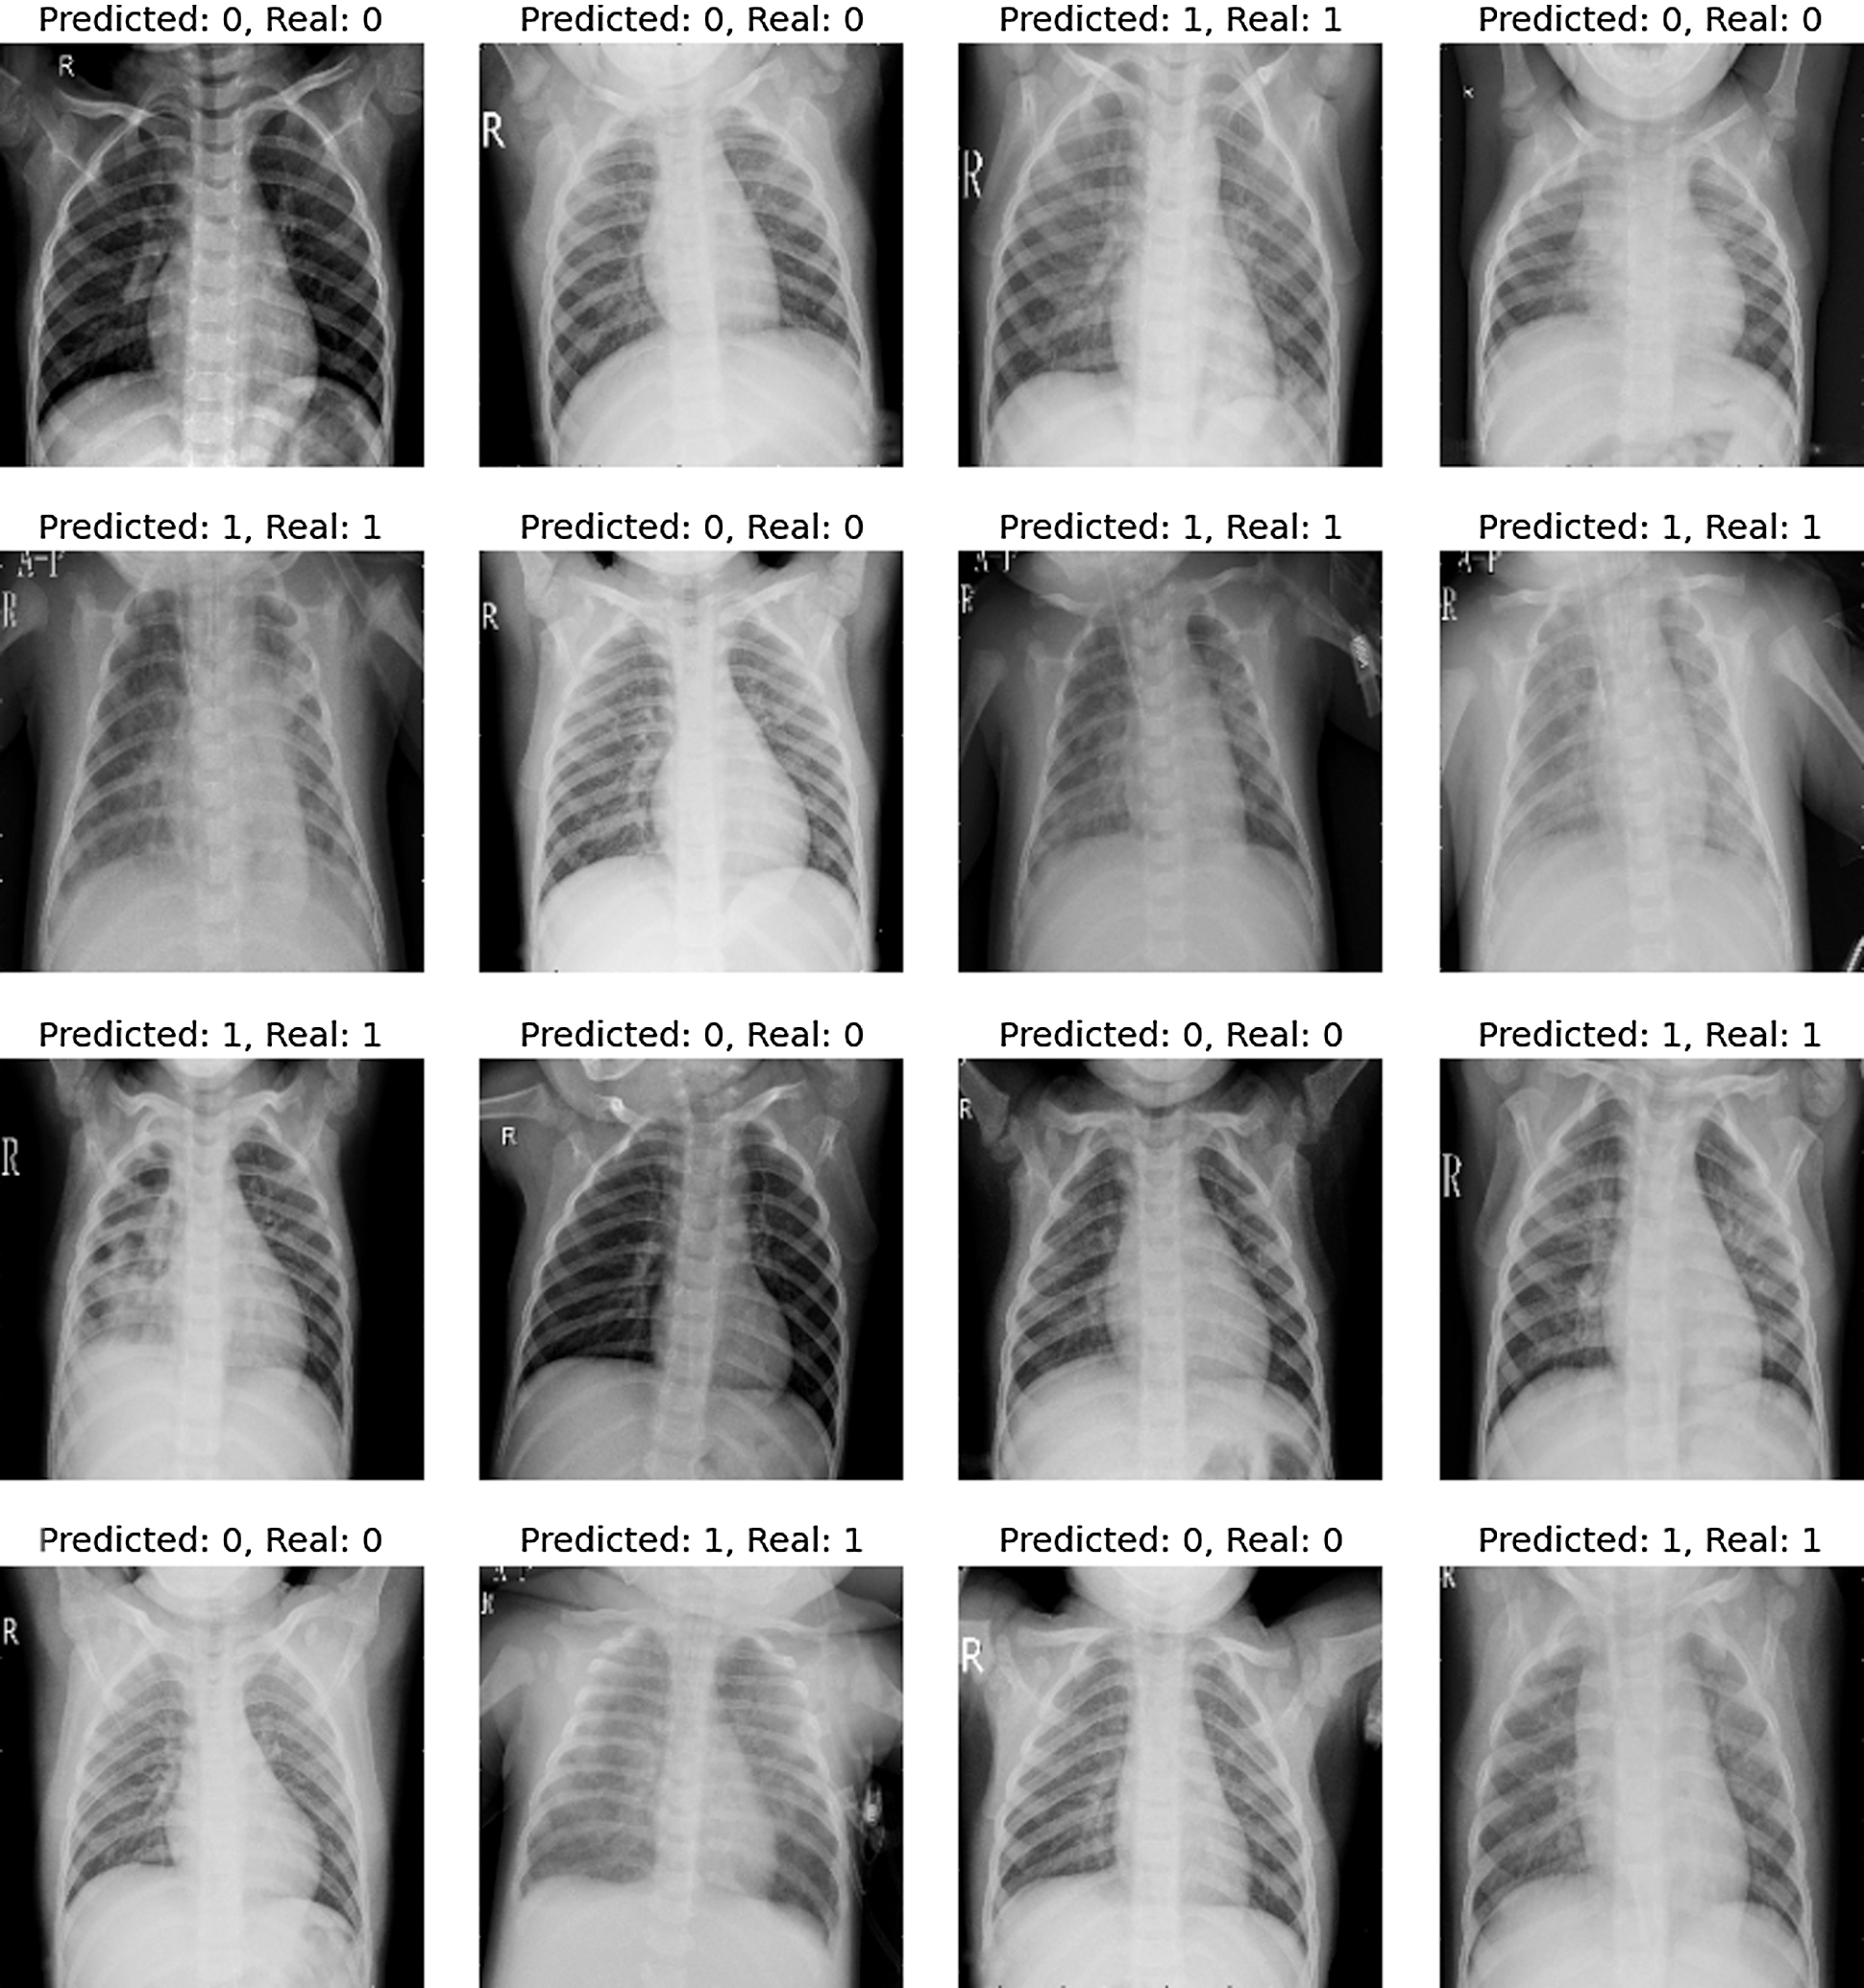

Fig. 12 shows the predicted CT scans results that ensure that the model is classifying the data accurately between the normal/healthy and the COVID-19 infected patients.

Figure 12: Results predicted and real